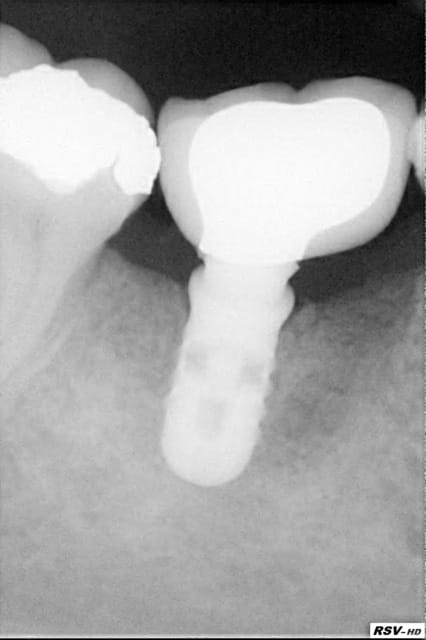

Un "vieux cas" LEONE qui se passe bien malgré des conditions de départ et de chirurgie pas au mieux! 4 ans déjà et aspect sympa très stable dans le temps. une de mes extractions implantation immédiate en site "pas idéal".La chronologie en rx.